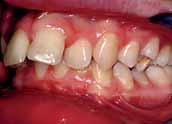

The patient had moderate Class II skeletal pattern with average Frankfort-mandibular planes angle and lower anterior face height. There was no facial asymmetry and the lips were incompetent with the lower lip trapped at rest behind the upper central incisors (Figure 1).

The oral hygiene was fair but needed improvement prior to orthodontic treatment. All teeth from the left permanent second molar to the right have erupted in both the upper and lower arches. The patient had carious lesions in both upper first molars, upper left second molar and lower left first molar. The maxillary arch was spaced with a midline diastema. Furthermore, there was mild lower labial segment crowding (4mm). The incisor relationship was Class II division 1, the overjet was 12 mm whereas the overbite was increased and complete to the palate

and causing trauma to the palatal mucosa. The centrelines were coincident and the buccal segment relationship was 1/2 unit Class II on both sides (Figure 2).